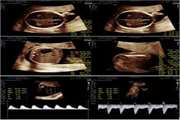

اتساع عروق کرونری قلب (CAE): گشادی غیرطبیعی رگ‌های خون‌رسان قلب و پیامدهای آن

اتساع عروق کرونری به معنی بزرگ شدن غیرطبیعی رگ‌های قلب است که می‌تواند باعث اختلال در جریان خون و افزایش خطر حملات قلبی شود. این وضعیت ممکن است ناشی از التهاب، آسیب یا بیماری‌های دیگر باشد. کنترل عوامل خطر و درمان مناسب برای کاهش عوارض حیاتی است.